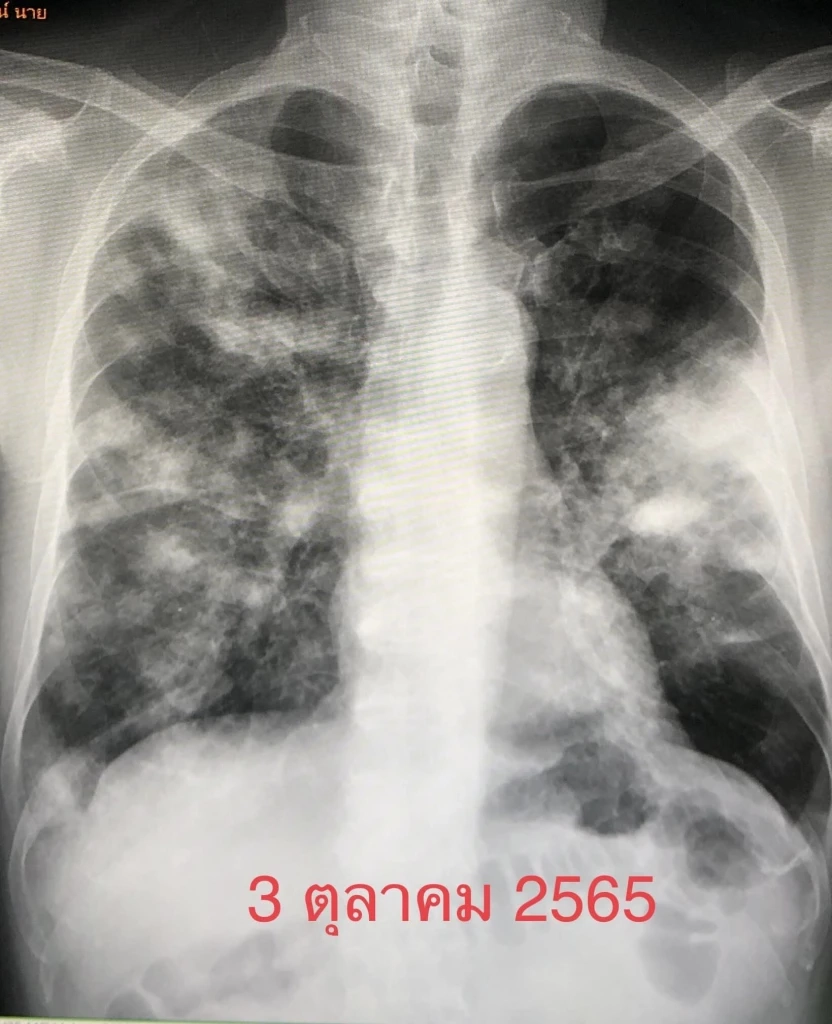

เริ่มไอแห้งๆ 3 สัปดาห์ เบื่ออาหารน้ำหนักลด 2 กิโลกรัม เหนื่อยบ้าง มาพบแพทย์วันที่ 3 ตุลาคม 2565

ตรวจร่างกาย ผอมลง เอกซเรย์ปอดมีฝ้าขาวทั้ง 2 ข้าง เอกซเรย์ปอดครั้งก่อนวันที่ 18 กุมภาพันธ์ 2563 ปกติ ทำคอมพิวเตอร์ปอดเห็นฝ้าขาวทั้งปอดซ้ายและปอดขวา

ค่ามะเร็ง CEA ในเลือดสูง 7.4 เจาะชิ้นเนื้อจากปอดด้านซ้าย ส่งตรวจไม่พบเชื้อวัณโรค ไม่พบเชื้อรา ตรวจทางพยาธิวิทยา พบเป็นมะเร็งปอดชนิด adenocarcinoma

สรุป: ผู้ป่วยเป็นมะเร็งปอดระยะสุดท้าย ส่งตรวจพิเศษไม่พบยีนกลายพันธุ์ ใช้ยามุ่งเป้าและภูมิคุ้มกันบำบัดไม่ได้ ผู้ป่วยไอ และเหนื่อยมากขึ้น ต้องใช้ออกซิเจนตลอดเวลา ให้เคมีบำบัดครั้งแรกแต่รับไม่ไหว เสียชีวิตอย่างสงบในรพ.วันที่ 20 พฤศจิกายน 2565"